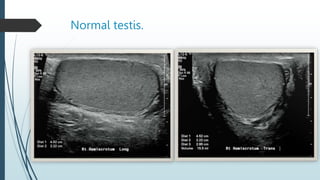

Ultrasound

The normal testes have a homogeneous,

moderately echogenic pattern.

 A testis is surrounded by a thin echogenic

fibrous band, which represents the visceral

component of the tunica vaginalis and the tunica

albuginea.

 In the absence of intrascrotal fluid, the tunica is

usually visualized only at its hilum as an

echogenic structure, where it invaginates into the

testis, to form the mediastinum testis.

Normal testis.

Normal testis